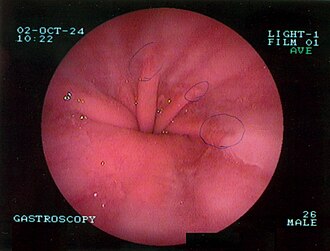

Dijagnosticira se gastroskopijom ili RTG pregledom želuca u Trendelembergovom položaju koji pokaže ulazi li želudac u grudni koš.